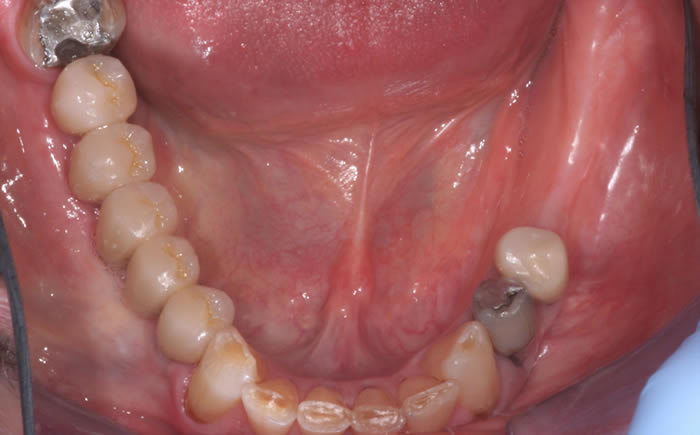

More back teeth replaced by dental implants

Case Three (2 images)

Case Four (4 images)

Case Five (4 images)

Case Six (8 images)

Case Seven (4 images)